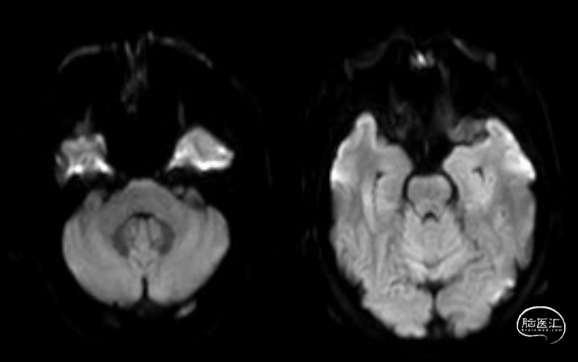

术前MRI-DWI显示延髓偏左侧亚急性腔梗灶,脑干偏右及右侧基底节区软化灶,脑干、双侧额顶叶、基底节区少许缺血灶。